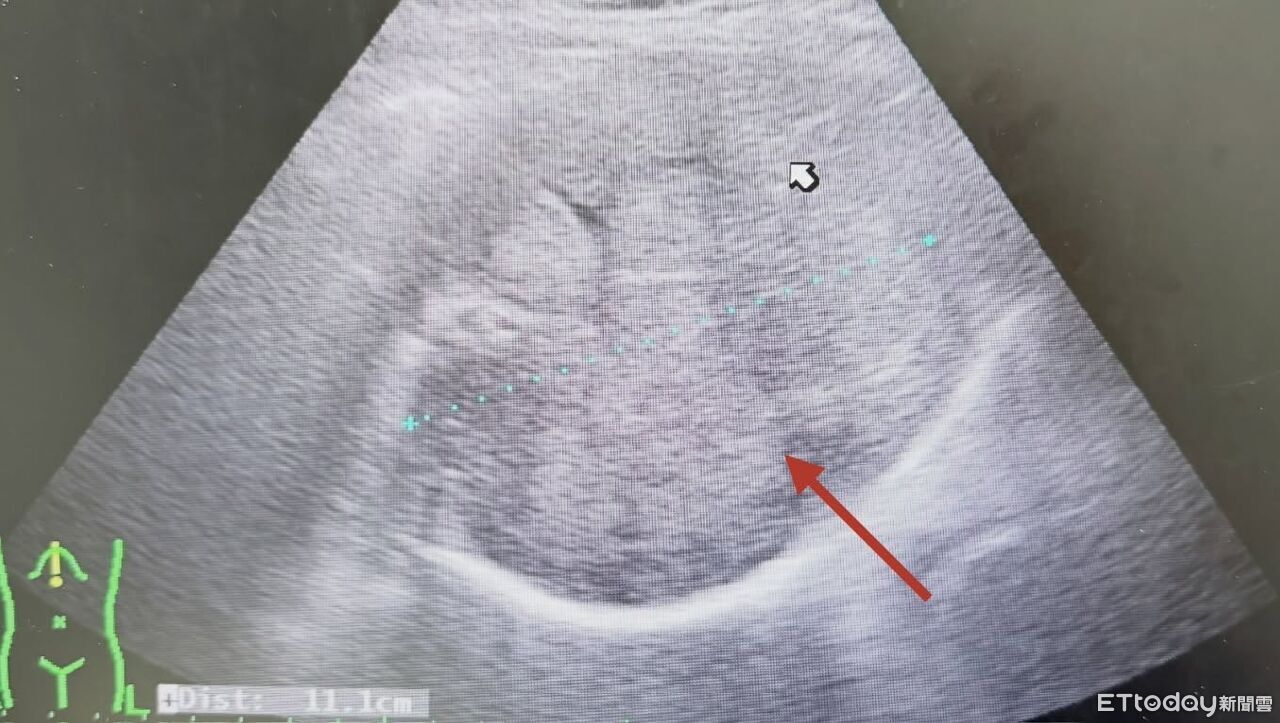

▲醫師以超音波一掃,發現患者的肝臟又被腫瘤塞爆了。(圖/張靖醫師授權提供,未經同意請勿任意翻攝)

有不少人以為腫瘤只要手術切除就畢業了,但若忽略術後追蹤,恐後果慘烈。胃腸肝膽科醫師張靖分享,近日收治一名上腹不適的患者,一照超音波赫然發現「無數的腫瘤」正密密麻麻地佔據整個肝臟。追問病史才發現,他雖然7~8年前曾開刀切除腫瘤,但術後自覺無礙就沒再回診,如今慘況連醫師都忍不住搖頭。